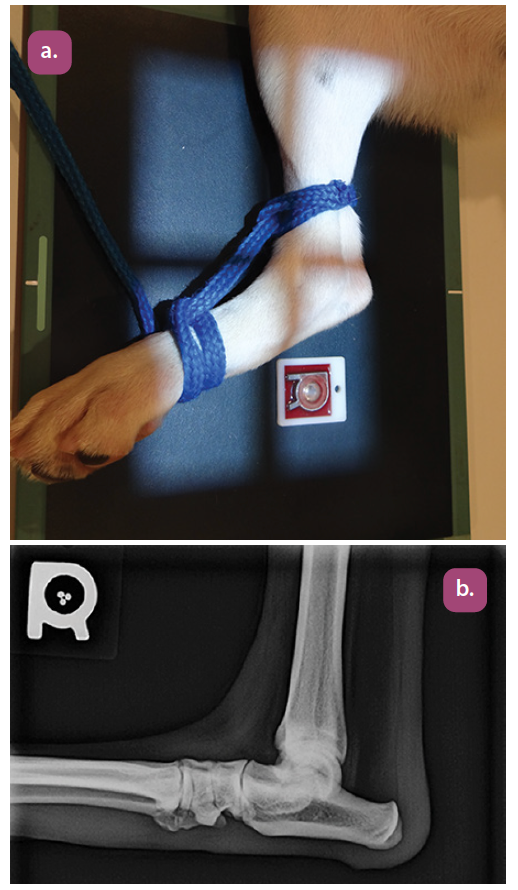

mediolateral projection of the tarsus

dorsoplantar projection of the tarsus

mediolateral projection of the elbow

craniocaudal projection of the elbow

flexed mediolateral projection of the elbow